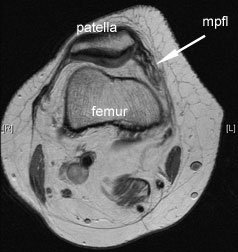

Those patients with normal anatomy are those whose kneecap sits in the trochlea, the tissues are all tensioned appropriately, the patella is the right shape, the trochlea is the right shape and their leg is straight. Then they have an accident where they fall over and they rupture the structures on the inside of the knee. The most important stabilising structure that they rupture on the inside of the knee is the medial (inner) patellofemoral ligament (MPFL), the ligament that goes from the thigh (femur) to the patella. This kind of injury is quite common, and often patients will be mis-diagnosed as having ruptured their ACL. One has to be very careful to ensure that the whole problem is not related to an unstable kneecap with a rupture of the medial retinaculum and MPFL.

The MPFL reconstruction is a reconstruction of the medial patellofemoral ligament. This ligament is often torn or stretched when patients dislocate their kneecap and its deficiency renders the patella unstable. MPFL reconstruction is presently a very popular talking point amongst surgeons. Various reconstruction techniques are being discussed with enthusiasm, much in the same way as ACL surgery was talked about 10-15 years ago. For MPFL reconstruction, we use one of the smaller hamstrings tendons (gracillis tendon). This tendon is only 3-4 mm in diameter and is borrowed through a small incision just below the knee.

There are many ways of doing this operation, but most surgeons now fix the new ligament either through a little tunnel in the patella by drilling a small hole through the kneecap on the medial side which the tendon is then passed through. The new ligament is then fixed with a little screw to the femur under appropriate tension, thereby re-creating the MPFL ligament. I usually use a metal screw as I found that the ‘dissolving’ screws do not work as well. This procedure works extremely well and stabilises the kneecap immediately. The post-operative rehab is extremely quick. It is a day-case operation - you come in and go home again either the same day or the next day. No knee brace or crutches are needed, although sone patients prefer to use crutches for the first few days. The physiotherapy starts soon and the aim is to regain knee flexion (bendind) as soon as possible. It is just the first 20-30 degrees of flexion that you need for the kneecap to engage in the trochlear groove of the femur – once it is in this groove it stays in the groove. Not that many surgeons are that comfortable doing an MPFL reconstruction because it is quite new, so we get referrals from far afield to do this operation which is actually relatively straight forward.